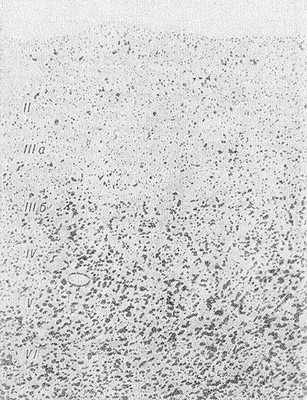

Рис. 2. Микропрепарат коры головного мозга при болезни Пика: резкое уменьшение числа клеток в верхних (II, IIIа) слоях коры головного мозга; окраска по Нисслго; х 18.

Гистологически отмечаются прогрессирующие хрон, дистрофические изменения нервных клеток в виде сморщивания, атрофии, липофусци-новой дегенерации, заканчивающиеся цитолизом (см.) и приводящие к резкому диффузному, а иногда и очаговому опустошению, к-рое сопровождается выраженным заместительным глиозом за счет пролиферации в основном астроцитов и олигодендроглиоцитов (см. Глиоз). Клеточное опустошение особенно заметно в верхних слоях (II— IIIа) коры мозга (рис. 2). Характерные признаки П. б.— появление набухших баллоновидных клеток с центральным хроматолизом и эктопией ядра (рис. 3, а), напоминающих нейроны с первичным раздражением при аксональной реакции, иногда превращающиеся в сверхнабухшие гомогенизированные клетки, а также появление нейронов с аргентофиль-ными цитоплазматическими шаровидными включениями — тельцами Пика (рис. 3, б). По данным Эску-ролля (R. Escourolle, 1956), набухшие клетки встречаются приблизительно в 60% случаев П. б., тогда как аргентофильные включения — в 20%. Преимущественная локализация набухших клеток — III—V слои коры, нейронов с аргентофил ьными включениями — чаще всего гиппокамп. Однако эти изменения могут встречаться во всех образованиях мозга, подвергшихся атрофии, и даже в клетках ствола мозга.